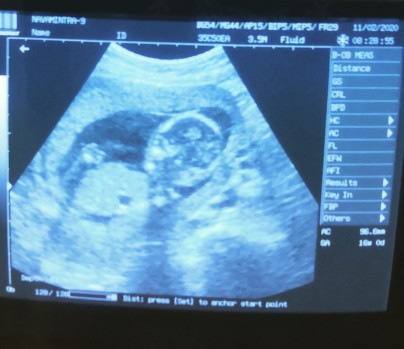

22 week 5 กรกฎาคมจ้า